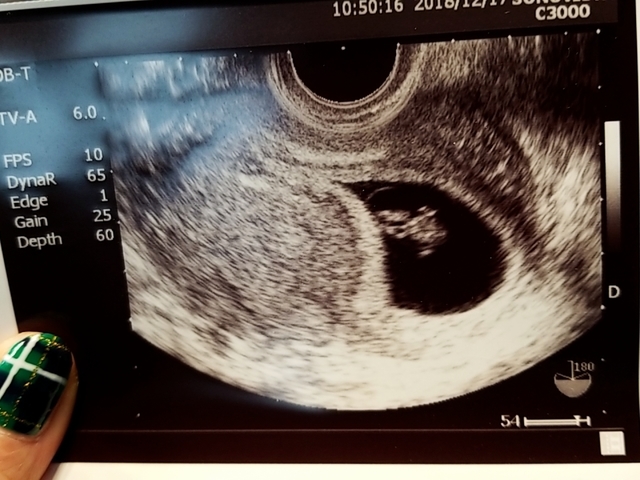

7週1日(7w1d・女の子)|ムーミンぴす さん(35歳)

エコー写真撮影時のエピソード:はじめての移植でできた子でした。

普通の妊娠と違って、早く妊娠がわかるので、健診の度に緊張していました。

エコー写真を見たときパンダみたい!と、すごく可愛いいと思いました。

15日前に見たエコー写真は胎嚢しか見えてなかったので、赤ちゃんが見れたことと、人間ってすごいと感動しました。